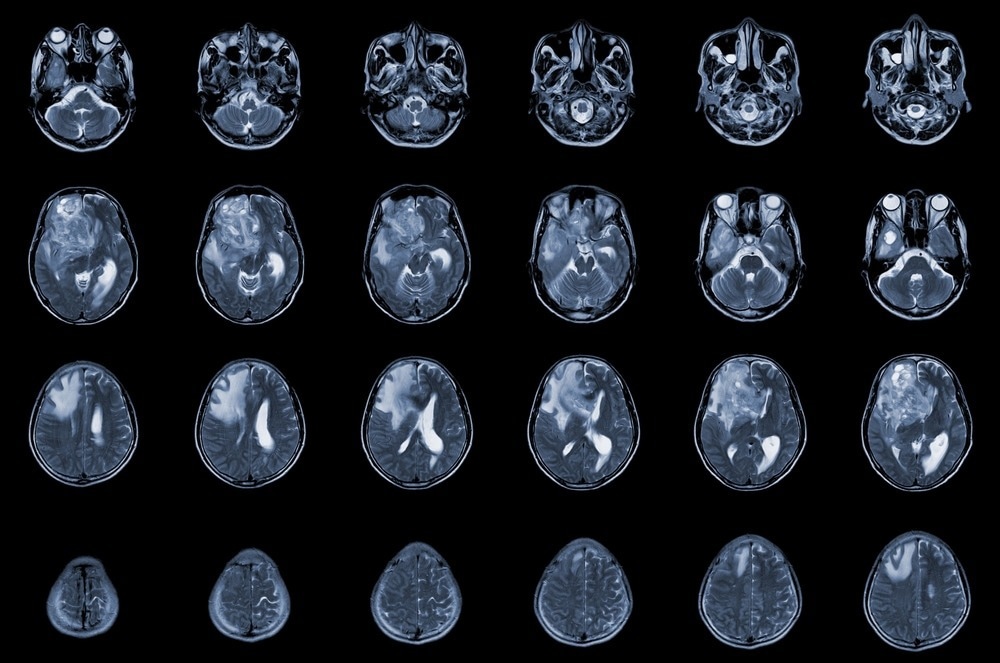

MRI brain axial view showing an isodense mass with ill-defined margins and surrounding edema in the right frontal lobe, consistent with glioblastoma and brain metastasis

Study: Gliocidin is a nicotinamide-mimetic prodrug that targets glioblastoma. Image Credit: April stock/Shutterstock.com